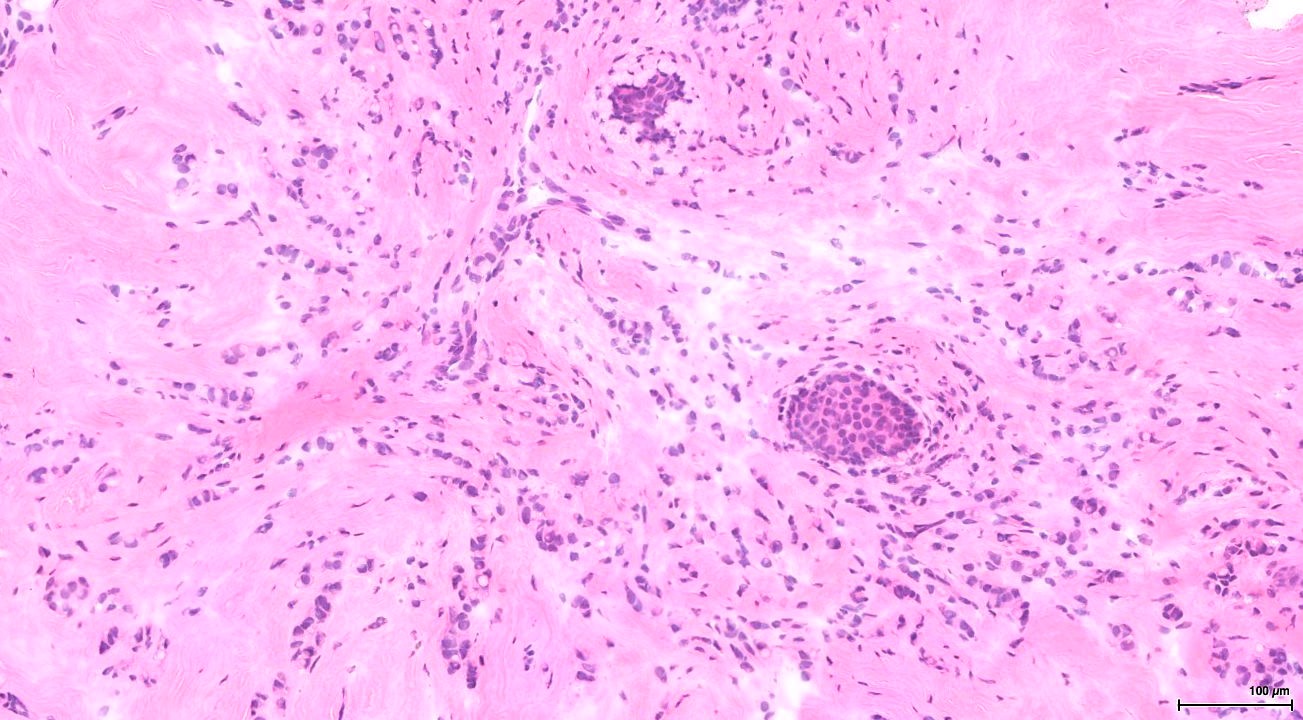

Cancer remains a global health challenge, necessitating innovative diagnostic approaches for early detection and understanding the underlying metabolic processes. Recent studies have uncovered links between cancerous tissue and depleted nitrogen isotope ratios (15N/14N) compared to healthy tissues, suggesting potential applications in diagnosis and cancer metabolism research. Limiting in most studies so far is the measurement sensitivity and design of sample selection. Traditional mass spectrometry methods require several mg of sample material. This poses a problem as biopsies contain many different components (i.e., samples do not consist of 100 % tumor cells and interferences with isotopic signatures of other components are likely). Most studies compared cohorts of cancer patients with cohorts of healthy patients, introducing biases from base line signatures in naturally occurring nitrogen isotopes. To overcome these limitations, we use a new high-resolution sampling method and a high-sensitivity analytical technique, enabling us to measure minute quantities of N. Our research focuses on studying nitrogen isotope ratios of diverse human cancers in individual patients to investigate the relationship between tumor types and grade, and effects on cellular nitrogen metabolism. An improved understanding of malignant cell nitrogen metabolism is central to an understanding-based attack on cancer and development of possible treatment strategies.